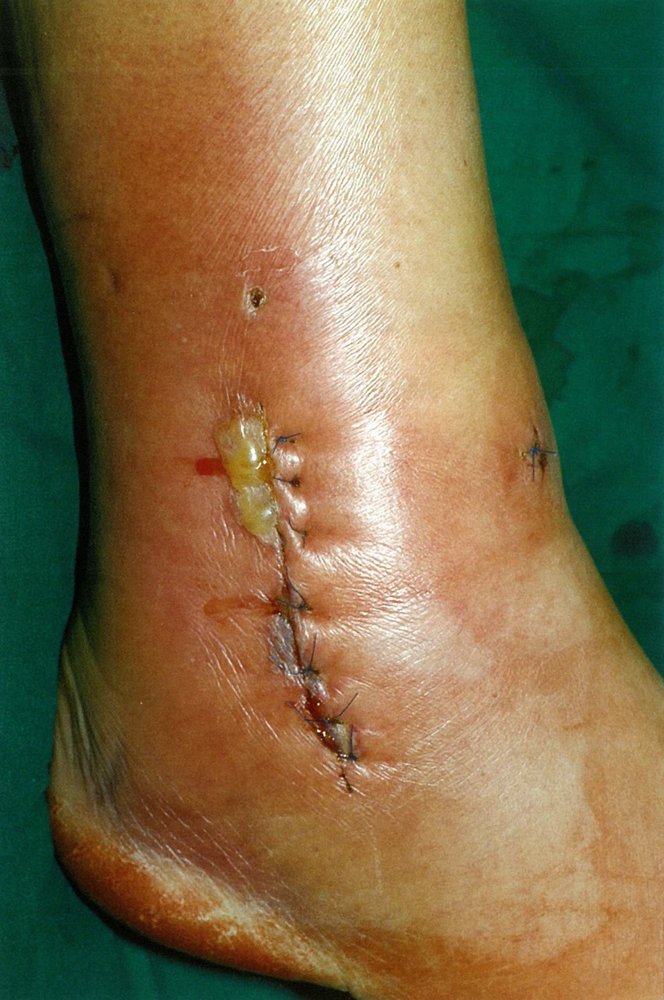

- Sources of sepsis, e.g., infected wounds, gangrene [17]

Iatrogenic changes: e.g., catheters , tubes, implanted devices, stomas , and other surgical sites, scars, and dressings